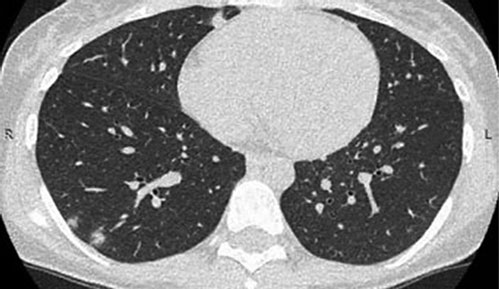

В тот же день была проведена компьютерная томография органов грудной клетки: в обоих лёгких выявлены очаги уплотнения лёгочной ткани (рис. 3).

Рис. 3. Компьютерная томография органов грудной клетки. Визуализируются очаги инфильтрации лёгочной ткани